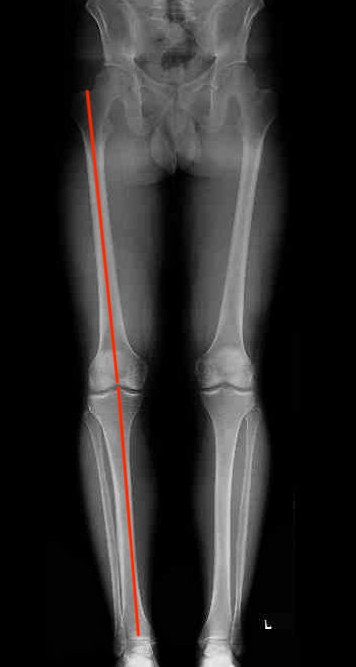

Medial cartilage restoration procedures

Correct to normal alignment

- anatomical axis 5 - 7o

- mechanical axis 180o

- lateral 30 - 40% of the lateral plateau

Example of medial cartilage procedure

- anatomical angle 0o

- correct to 5o valgus

- need to correct 5o